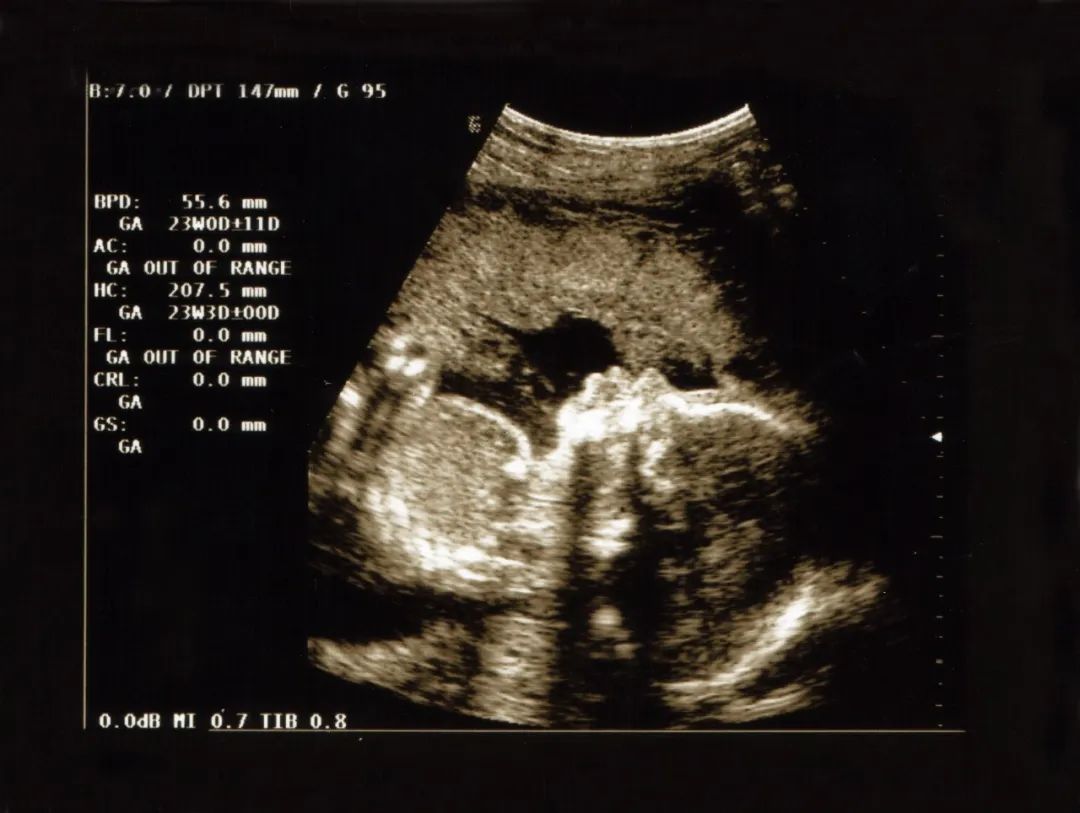

实际上很多胎停,都是在孕检的时候检查出来的,一般停经怀孕8周后,超声检查尚未探及胎心波动,就很有可能是胎停。

如果没有在B超重检查出胎停,那么唯一的征兆可能是怀孕症状消失,比如恶心、乳房胀痛、疲劳等症状,都好了。

如果在孕10周左右出现这种情况,可能是胎停的征兆。